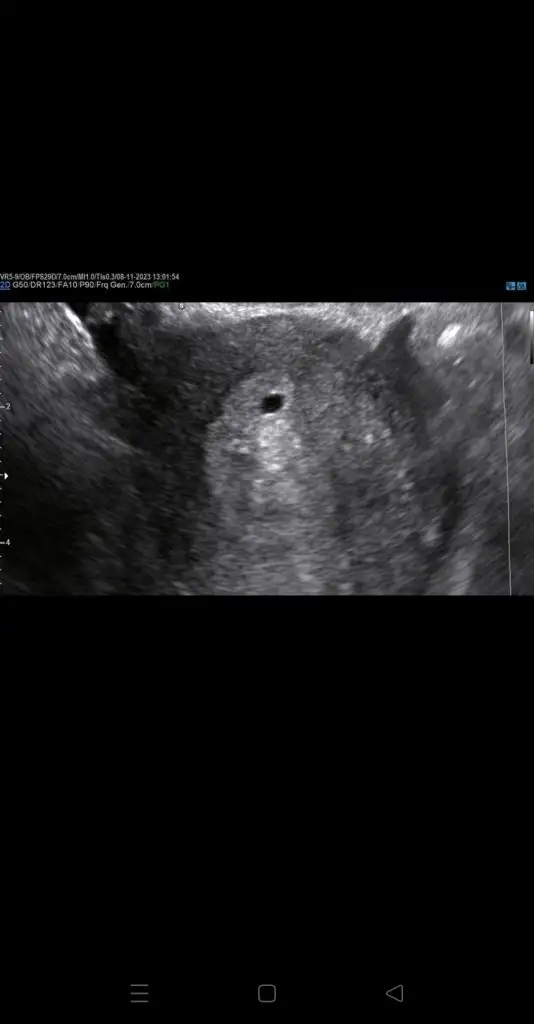

Merhaba arkadaşlar ben bugün çok stresli bir gün geçirdim. İki kez dış gebelik yaşayan birisi olarak herzaman gittiğim özel doktoruma gittim.ilk gittiğimizde keseyi vajinada gördü. üç gün sonra gittiğimizde karnimdan gördüğünü çok küçük dediğini bir üç gün sonra tekrar gelmemi istedi.biz eşimle gittik bugün baktığında karnımda bana bu kese nerede dedi sonra ufak birşey gördüğünü fakat bu arama uzun bir süreçte oldu sagliksiz bir gebelik dedi. Siz bugün ve iki gün sonra beta HCG değeri verin dedi düşerse kürtaj yaparız dedi. Eşim bu işte başka birşey var deyip bir baska doktora götürdü. Doktorumuz diğer doktorun yapmadigi kontrolleri yaptı eski doktora kalsak kürtaj olacaktım iki gün sonra eşim sayesinde gittiğim doktor kese güzel oluşmuş ne bir kanama nede başka birşey var dedi ama kese boyutunu bilmemekle beraber bu doktor rahatça gördü. Fakat bebek içinde yoktu. Haftaya gideceğim doktora .şimdi burada okudum 6 yada 9 hafta içinde bebek görünebilir diye doğrumu ? Ayrıca bugün beta HCG değerim 8345 beş haftalık degerim buraya kese goruntum de attim